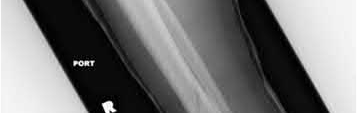

What is the most common type of malalignment after intramedullary nailing of distal 1/3 extra-articular tibia fractures using a infrapatellar approach when compared with plating?

The most common type of malalignment after intramedullary nailing of distal 1/3 extra-articular tibia fractures using an infrapatellar approach when compared with plating is valgus malalignment.

Fixation of distal one-third tibial shaft fractures can be successfully treated with either intramedullary nailing or plating. The literature describes advantages and disadvantages to both approaches, however intramedullary nailing has been shown to lead to increased rates of valgus malunion. Recent studies have shown that using a suprapatellar approach may decrease the incidence of valgus malalignement.